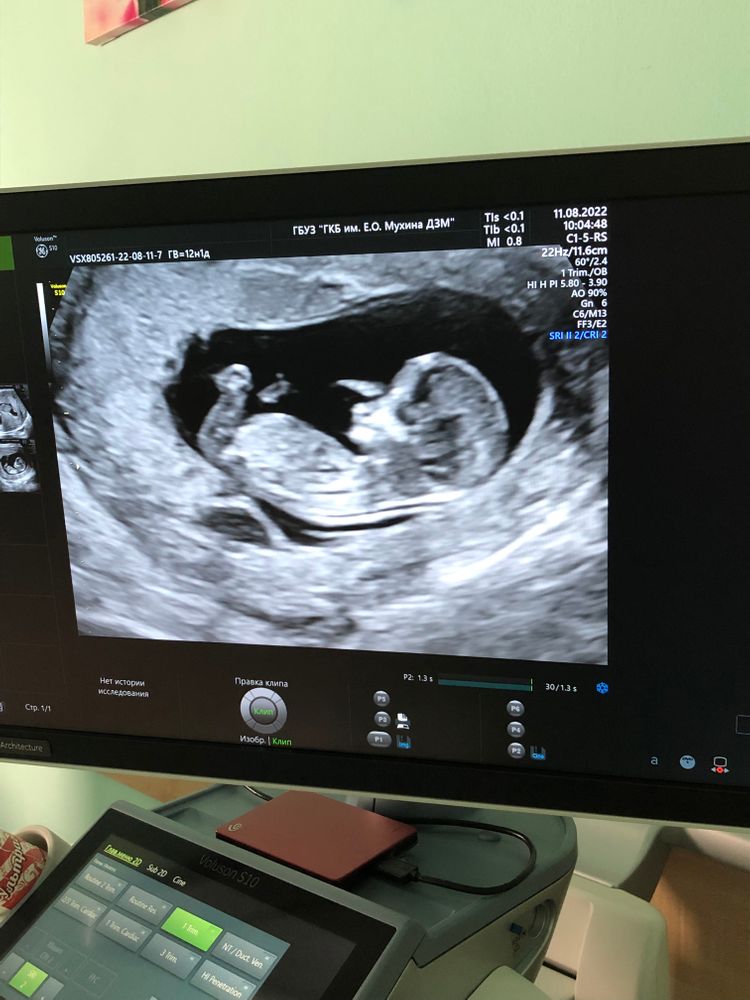

Кто в домике живет?

Не видно половой бугорок, поэтому непонятно.

Девочка🤗 Мочевой пузырь прямо под бугорком))

10-11 недель малыш/ка??? Метод Рамзи